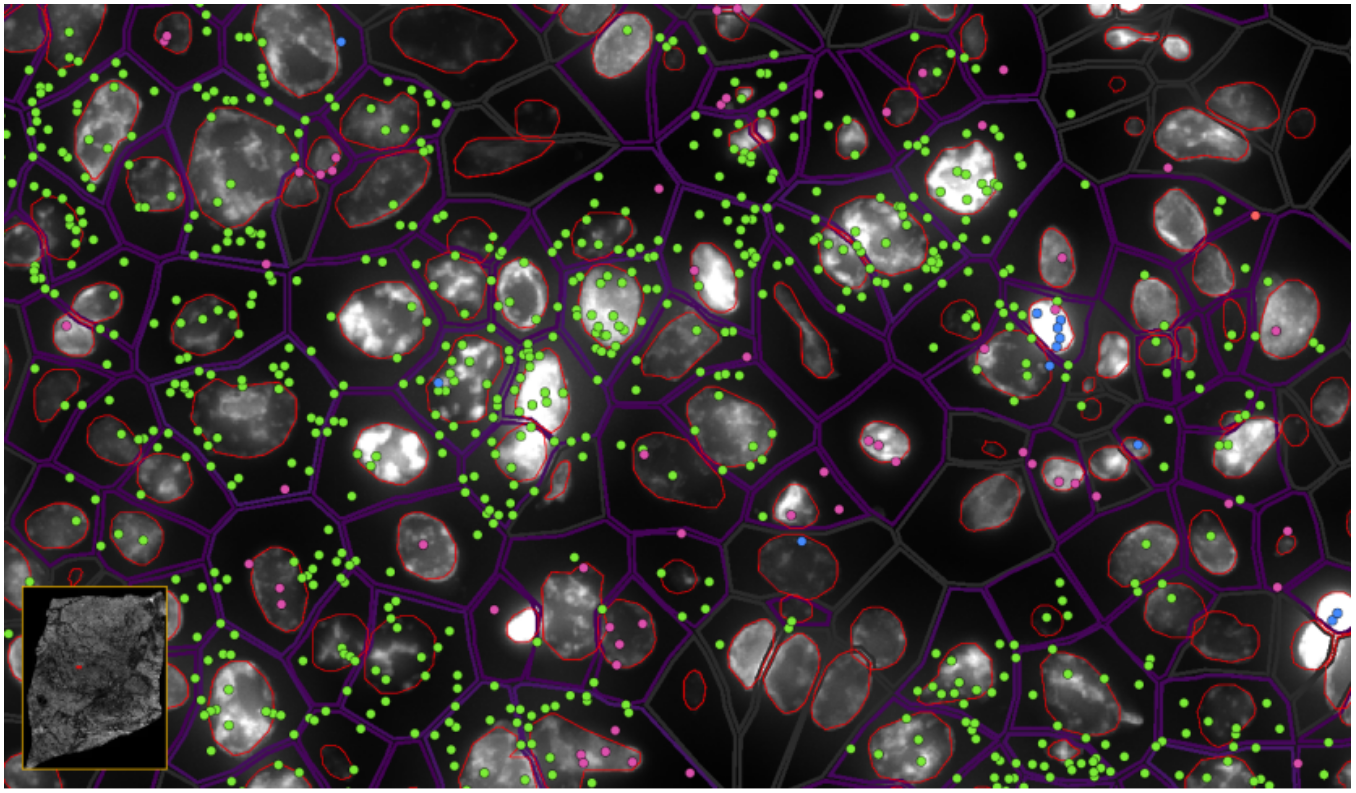

ͼ6-1£ºÊµÏÖµ¥Ï¸°û/ÑÇϸ°ûÇø·ÖÂʵĿռäת¼×éÆÊÎö£¬Â̵ã-EPCAM , À¶µã-KLRD1 £¬·Ûºìµã-LILRB2

ͼ6-2£ºÊµÏÖµ¥Ï¸°û/ÑÇϸ°ûÇø·ÖÂʵĿռäת¼×éÆÊÎö£¬Â̵ã-EPCAMת¼±¾